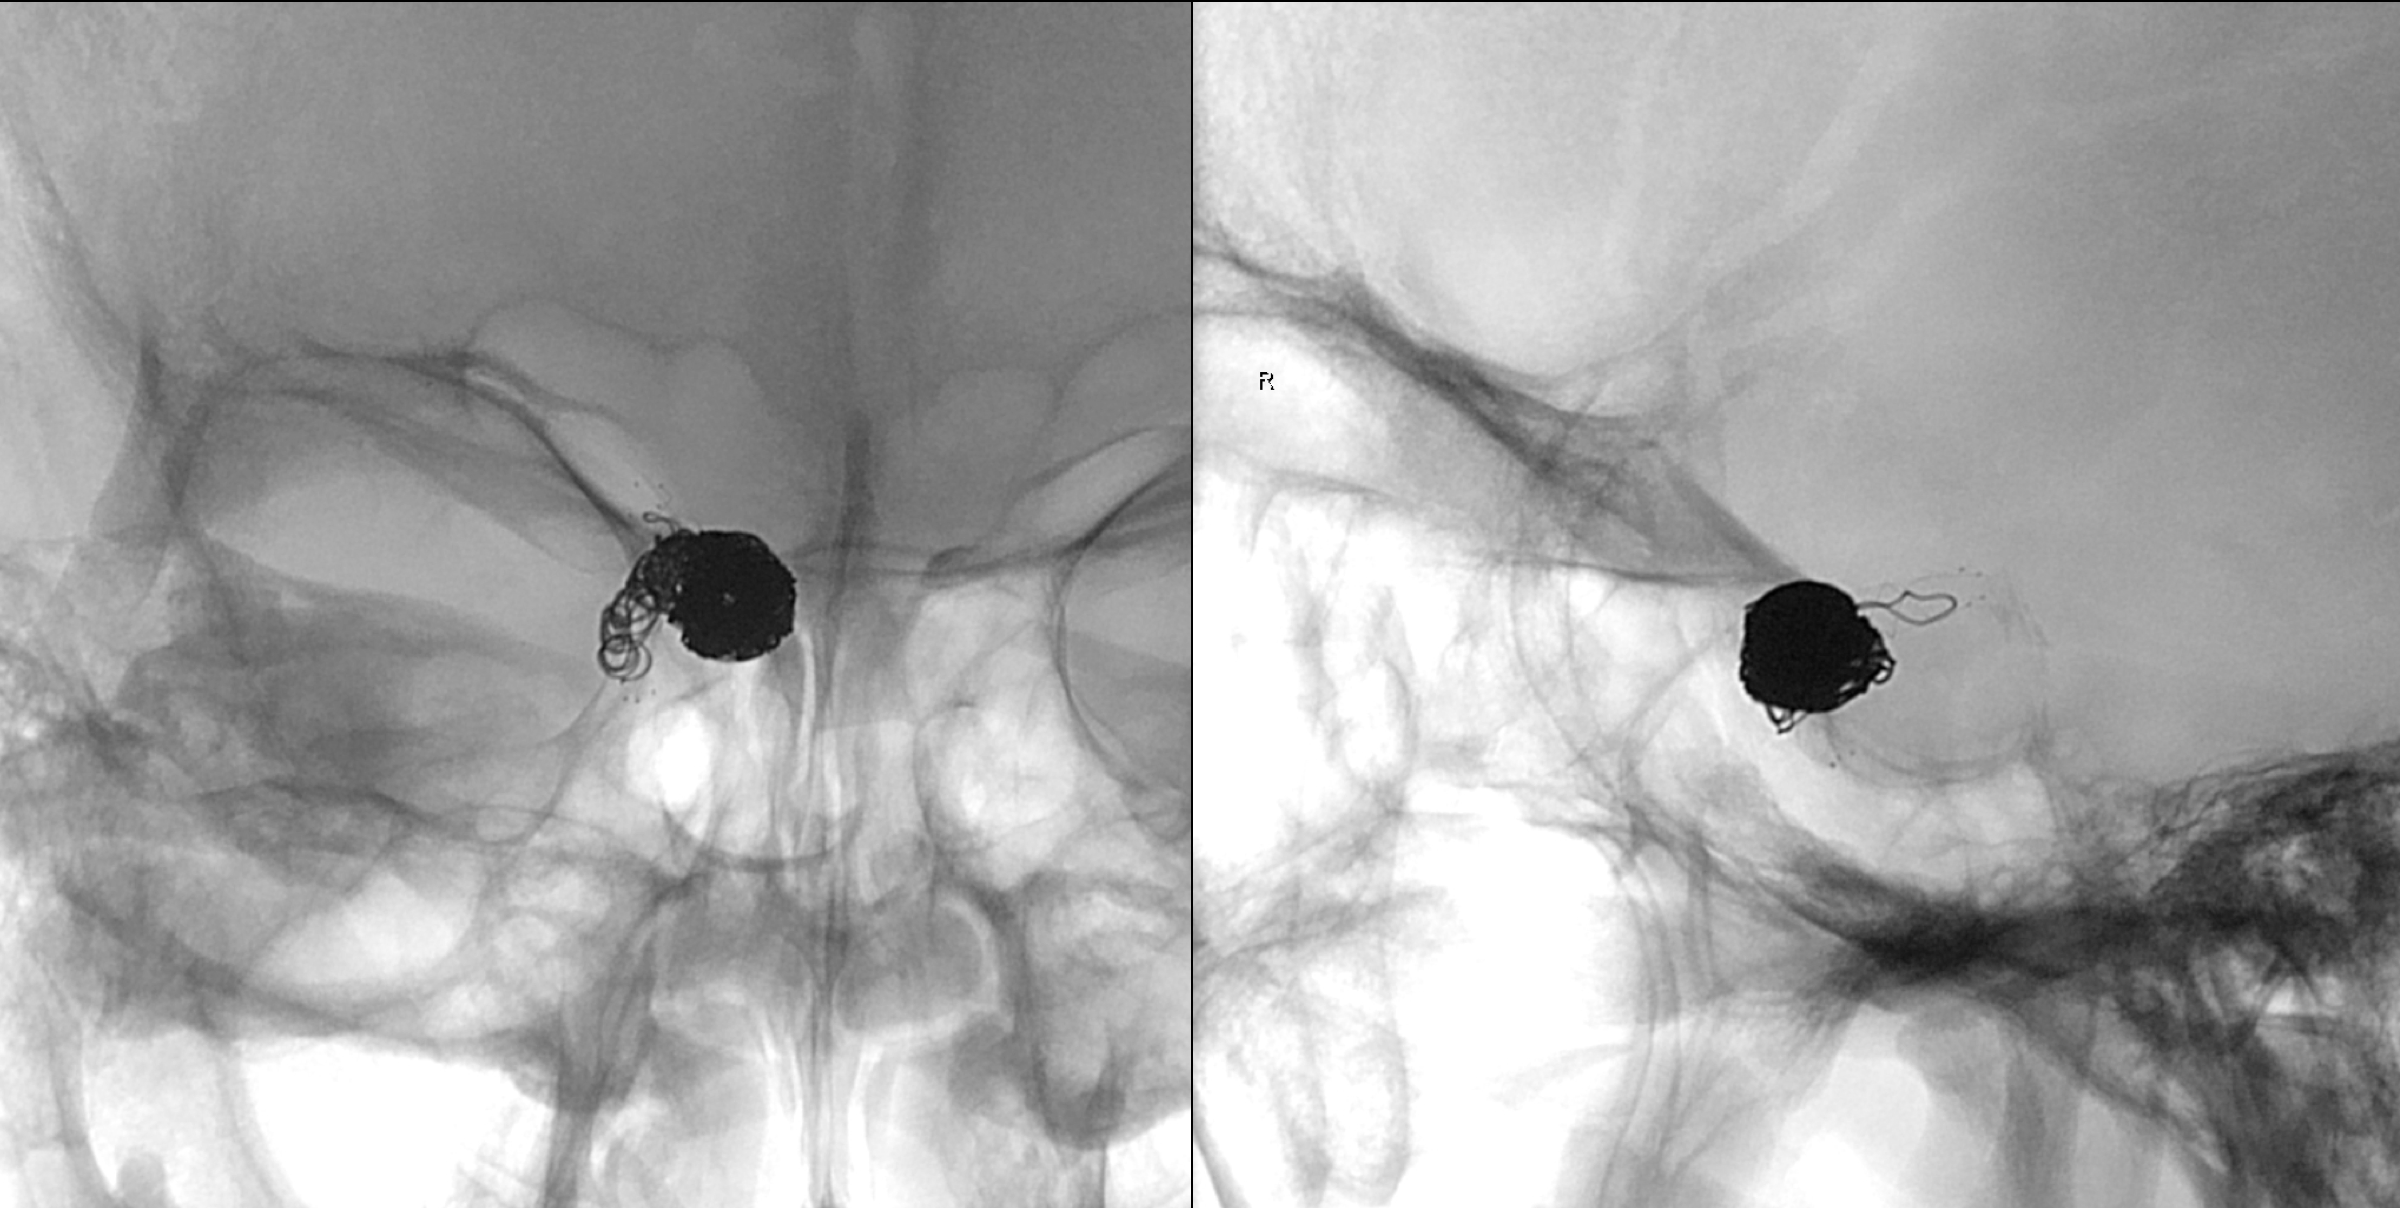

右侧颈内动脉正侧位造影:眼动脉段动脉瘤。

不同工作位造影:动脉瘤完全栓塞,载瘤动脉通畅。

术后正位造影及蒙片显示:动脉瘤完全栓塞!

术后侧位造影及蒙片显示:动脉瘤完全栓塞!

蒙片显示:支架贴壁良好!部分弹簧圈被支架贴附于近端瘤颈及正常颈内动脉内壁!

术后1年于2017年3月10日再次入院复查。右侧颈内动脉正位造影及蒙片显示:动脉瘤未见复发!

右侧颈内动脉侧位造影及蒙片显示:动脉瘤未见复发!

正侧位蒙片显示:支架及弹簧圈形态良好!